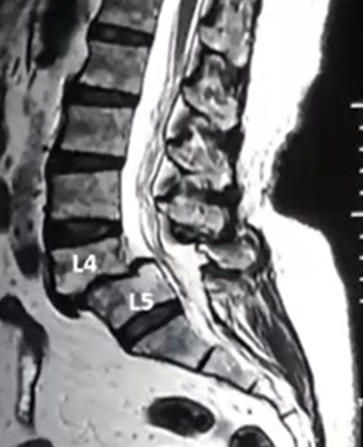

Spinal fusion is a surgical procedure that permanently joins two or more bones of the spine so they heal into one solid bone. This eliminates painful movement between them and stabilizes the spine.

The surgeon removes the damaged disc or diseased bone, places a cage or bone graft between the vertebrae, and secures it with screws and rods. Over months, the bones heal together naturally. The surgical approach (front, back, or side) depends on the patient's specific condition and body type.